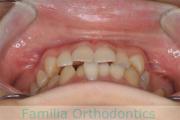

No.22V-029

- 叢生

- 上顎前突

- 19歳

- 男性

- 上:

- 8448

- 下:

- 主な使用装置:

- FEA 022

- 治療にかかった費用:

- 92万円

でこぼこを治したいということで来院されました。上下左右から親知らずも第一小臼歯も抜歯が必要で、歯科矯正アンカースクリューを併用して大臼歯を後ろに引っ張りながらの治療でした。3年弱、35回程度の通院が必要でした。

叢生が著しく、後戻りのリスクがあります。またアンカースクリューが必須のため、もしもスクリューが安定しないと、治療が難しく長くなってしまう恐れがありましたが、幸い脱落は見られませんでした。